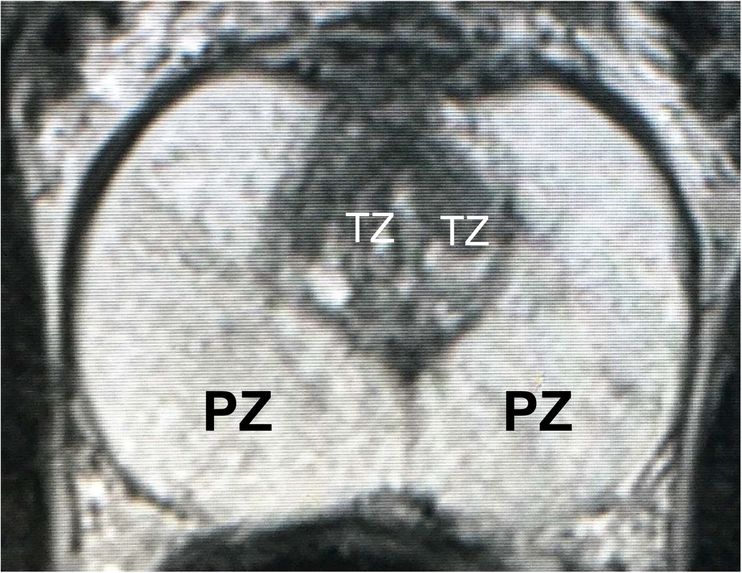

Figure 1: T2-weighted MRI at the maximal axial plane.

MRI of prostate cancer usually consists of two non-overlapping adjacent regions: the peripheral zone (PZ) and the transition zone (TZ). An example of prostate MRI with labelled zones is shown in Figure 1. Identifying prostate zones is important for diagnostic and therapies. However, the identification work requires substantial expertise in reading MRI scans. Therefore, automatic segmentation of prostate zones is instrumental for prostate lesion detection.